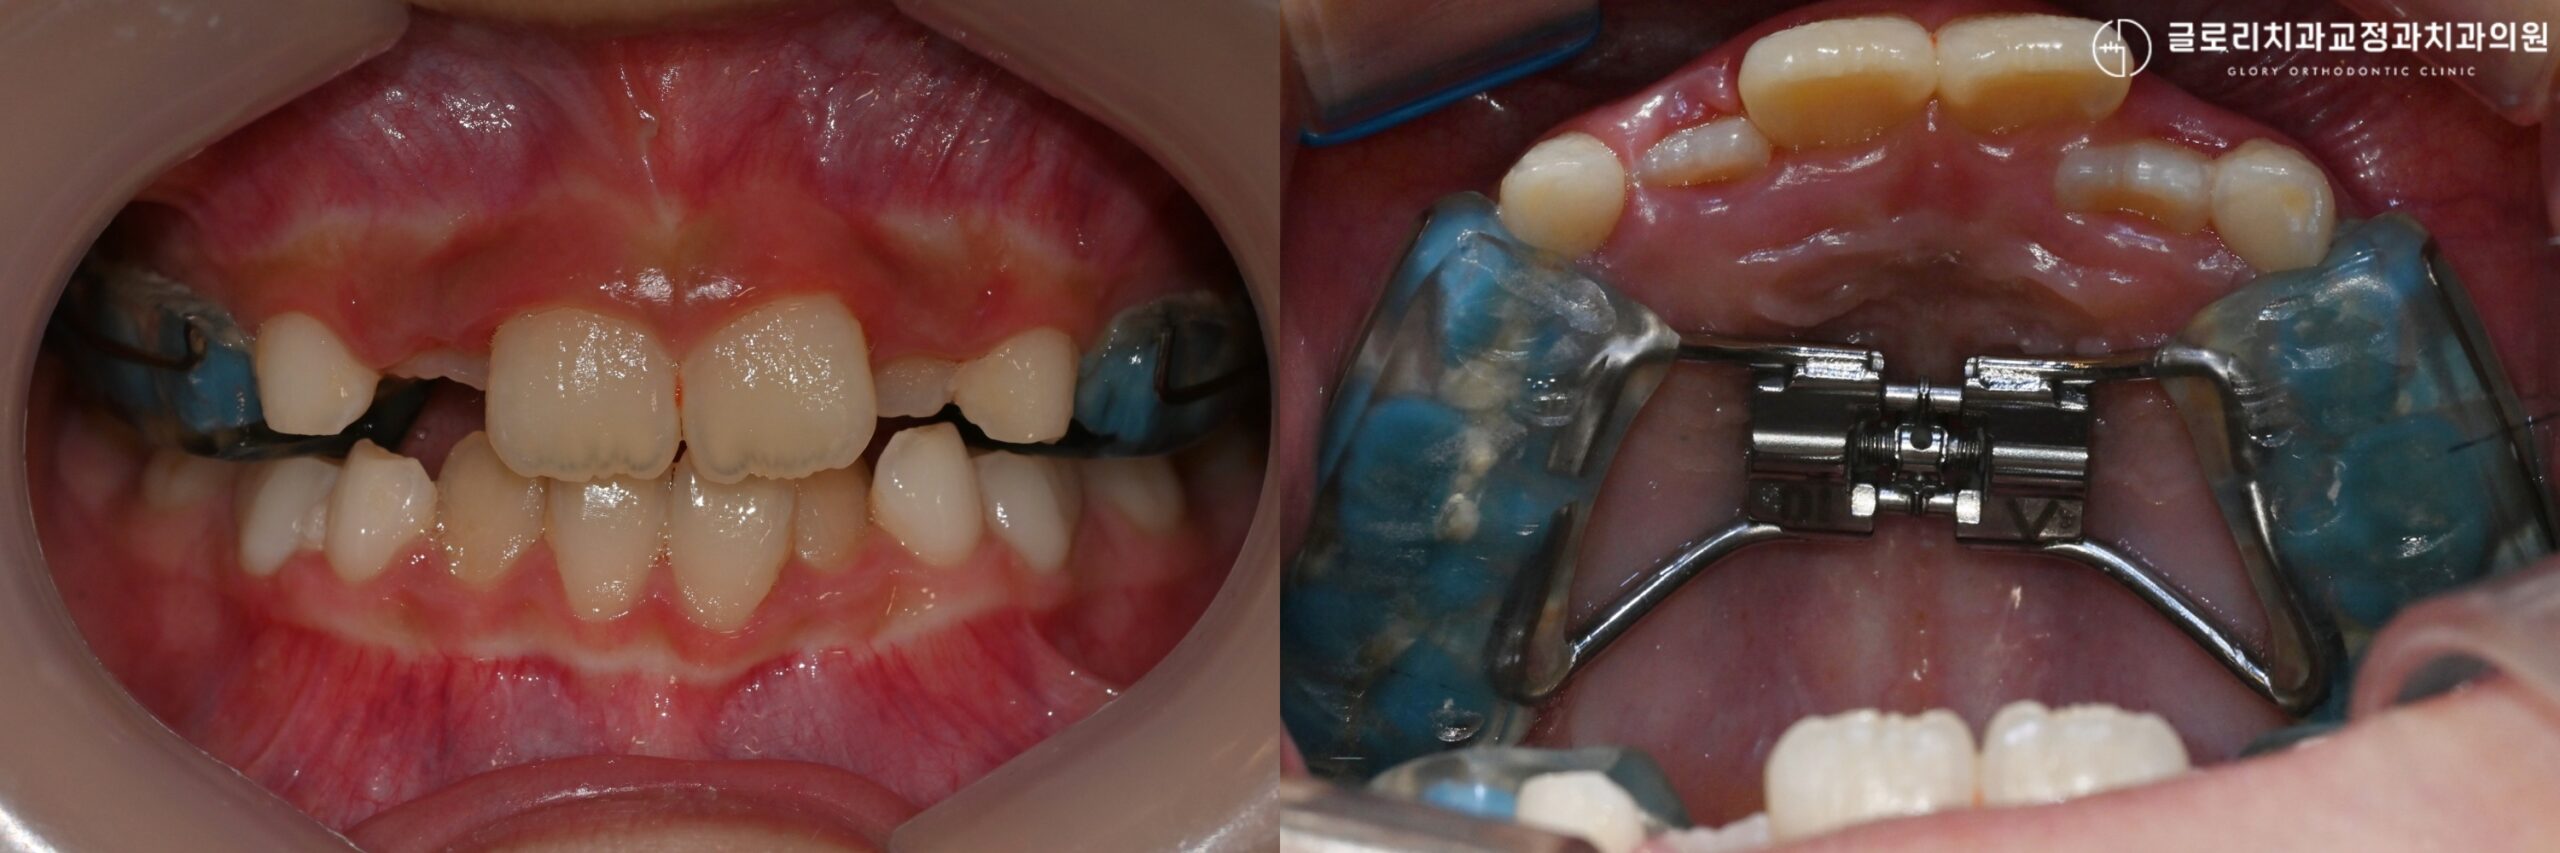

상악 확장장치와 하악 확장장치의 차이

아이의 구강 내부를 자세히 살펴보면 영구치가 나올 공간이 부족한 경우가 있습니다.

위아래 치아 사이에 맹출 공간이 협소하고 특히 입천장이 좁고 깊다면 상악골 확장 이 필요할 수 있습니다.

악궁은 치아가 배열되는 아치 형태의 뼈 구조로, 이 공간이 좁으면 치아들이 서로 밀리며 덧니가 생깁니다.

상악골 확장 치료를 진행하면 치아 배열 공간이 확보됩니다.

⁎상악골 확장의 원리

상악 확장장치는 위턱의 좁은 악궁을 넓혀주는 교정 장치입니다.

RPE(Rapid Palatal Expander)라고도 불리는 상악 확장장치는 입천장 중앙의 봉합선을 활용해 악궁의 폭을 증가시킵니다.

위턱뼈(상악)는 나비 모양처럼 좌우로 갈라져 있는 구조입니다.

*성장기 아이들은 이 봉합선이 아직 완전히 붙지 않아서 상악 확장장치의 효과가 성인보다 크게 나타납니다.

상악 확장장치는 구강 내에 고정되어 있어서 착용 시간을 따로 신경 쓸 필요가 없습니다.

정해진 주기에 맞춰 나사를 돌려주면 점진적으로 악궁이 넓어지며 공간이 만들어집니다.

⁎하악 확장장치, 슈왈츠란?

그렇다면 아래턱에도 상악 확장장치처럼 뼈를 넓히는 장치가 있을까요?

결론부터 말씀드리면 아래턱(하악)을 골격적으로 넓혀주는 장치는 따로 없습니다.

위턱과 달리 아래턱뼈는 이미 하나로 붙어 있는 형태를 갖고 있기 때문입니다.

아무리 물리적인 힘을 가해도 아래턱의 뼈는 서로 떨어질 수 없는 구조입니다.

즉, 하악에서는 골격적인 확장이 불가능합니다.

대신 안으로 쓰러진 치열을 바로 세워주는 방식으로 어느 정도 공간을 확보합니다.

이때 사용하는 것이 하악 확장장치인 슈왈츠(Lower Schwarz)입니다.

슈왈츠는 환자가 스스로 꼈다 뺐다 할 수 있는 가철성 장치에 해당합니다.

슈왈츠 장치에도 스크루가 달려 있어서 장치 속 스크류를 돌려주면 안쪽으로 기울어진 치아가 점차 바깥으로 세워집니다.

뼈 자체를 넓히는 것이 아니라 치아의 각도를 조절해 공간을 만드는 원리입니다.